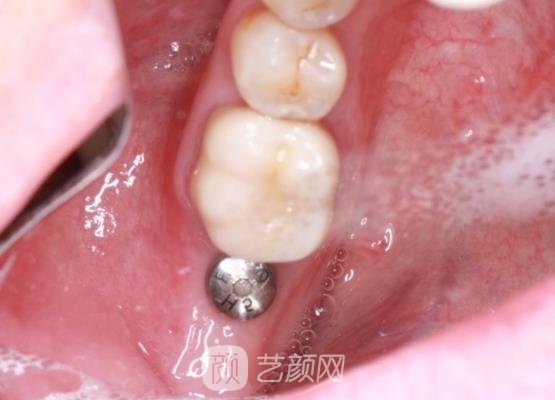

因为我有一颗牙齿损坏的程度比较严重,已经没有修复的必要了,所以医生告诉我可以先拔牙,然后再进行种植牙手术,这个样是比较方便的,也可以很有成果的解决我牙齿的问题。

再三决定后,我还是觉得医生推荐的方案是比较适合的,然后医生就帮我开始了手术,开始是拔牙,医生先是对我的牙龈处进行了麻醉的处理,手术的过程是比较快的,我也没有感觉到什么剧烈的疼痛感。

然后就开始种植牙齿了,这个时候可以感觉到医生一直在拿着医疗仪器在我的牙齿上钻孔打转,然后就是缝合我牙龈处的伤口,几个小时,手术过程就结束了。

结束手术的时候,我的牙龈处有一些肿胀的情况,但是也没有感觉到疼痛,敢医生告诉我肿胀的情况是比较正常的,然后给我开了一些消炎药提醒我定时服用。